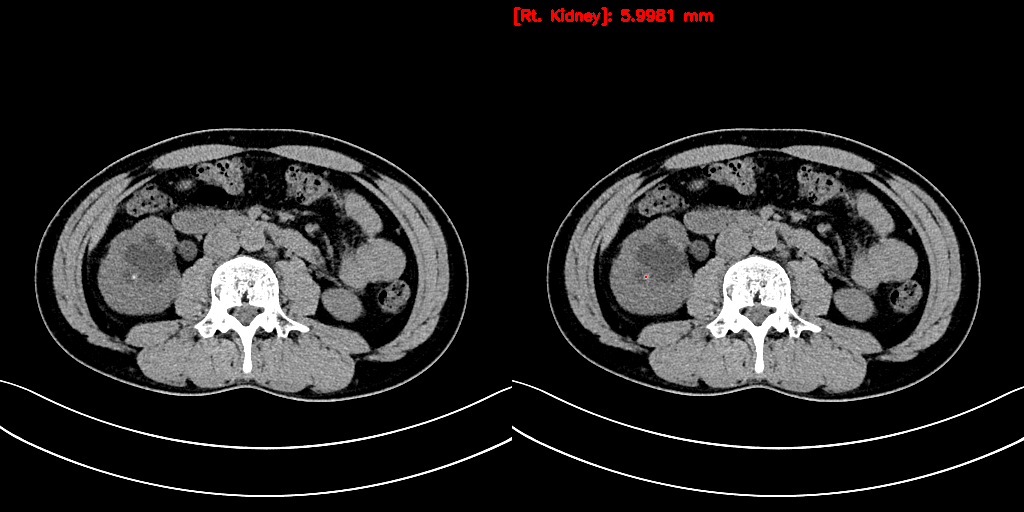

URO dot AI